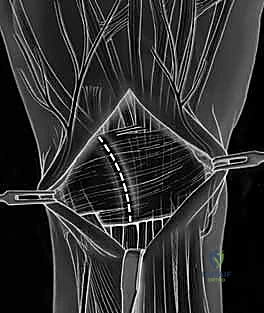

- Ligament-Splitting Capsulotomy: We'll perform a dorsal ligament-splitting capsulotomy, as described by Berger and Bishop. This approach is preferred because it preserves the integrity of the crucial dorsal radiocarpal and intercarpal ligaments, which are important secondary stabilizers.

- Identify Key Ligaments: First, identify the dorsal radiocarpal ligament (specifically the dorsal radiotriquetral ligament) and the dorsal intercarpal ligament. These form a "V" shape on the dorsal aspect of the wrist.

- Incision: The capsulotomy incision is made between these two ligaments, splitting the capsule longitudinally.

TECH FIG 5 • A. Dorsal ligament-splitting capsulotomy planned.

TECH FIG 5 • B. Dorsal ligament-splitting capsulotomy showing location of the dorsal radiotriquetral and scaphotriquetral ligaments.

* Reflection: Carefully reflect the dorsal capsule radially and ulnarly, creating two flaps. Use fine stay sutures or small skin hooks to retract the capsule, providing excellent visualization of the underlying carpal bones and ligaments.

TECH FIG 5 • C. Dorsal capsule reflected radially.

TECH FIG 5 • D. Dorsal capsule reflected radially s

> **Surgical Warning:** When elevating the capsule, it is absolutely critical *not to dissect too deep* over the region of the lunotriquetral area. The lunotriquetral ligament is intimately related to the radiotriquetral ligament, and aggressive deep dissection can inadvertently injure this crucial extrinsic stabilizer, potentially exacerbating carpal instability. Maintain a superficial plane while reflecting the capsule.